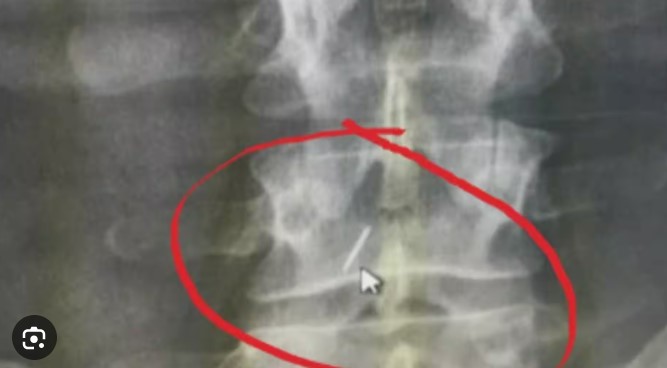

2010 में, एक अन्य अस्पताल के स्कैन में उसके पेट और रीढ़ की हड्डी के बीच एक विदेशी वस्तु का पता चला। इसके बाद, तीसरे अस्पताल में एक शल्य प्रक्रिया के माध्यम से उसकी रीढ़ की हड्डी में फंसी 3.2 सेमी की सर्जिकल सुई को निकाला गया। अगले वर्ष, उसने उपभोक्ता फोरम में शिकायत दर्ज कराई। दीपक अस्पताल और इलाज करने वाले दो डॉक्टरों ने दावा किया कि पद्मावती की शिकायत मनगढ़ंत है और इसे खारिज किया जाना चाहिए। उन्होंने शिकायत दर्ज कराने में सात साल की देरी पर भी सवाल उठाए।

सभी पक्षों की दलीलों की समीक्षा करने के बाद, उपभोक्ता फोरम ने निर्धारित किया कि शिकायतकर्ता ने दीपक अस्पताल और दो डॉक्टरों, डॉ. शिवकुमार और डॉ. एचएन नागराज द्वारा चिकित्सा लापरवाही स्थापित की है। फोरम ने दीपक अस्पताल, डॉ. शिवकुमार और डॉ. एचएन नागराज को मुआवजा देने के लिए जिम्मेदार ठहराया और बीमाकर्ता को 5 लाख रुपये का भुगतान करने का निर्देश दिया।